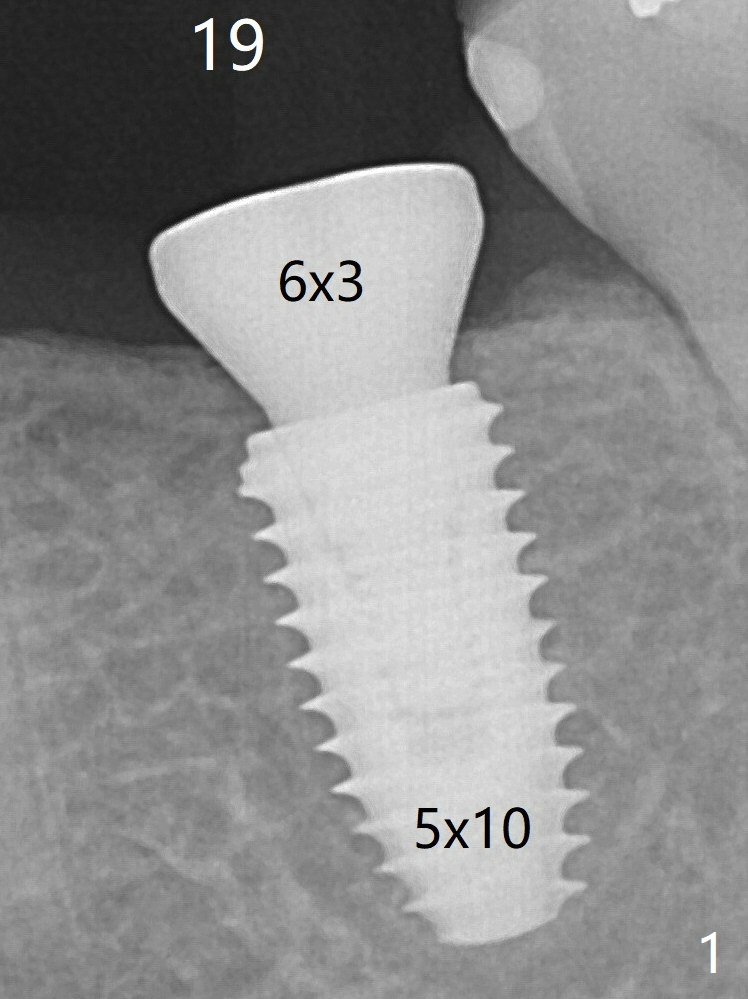

A 5x10 mm implant is intentionally placed distal at #19 using guided surgery (Fig.1).  When it is osteointegrated, it will be used as an anchorage to upright the tooth #18 orthodontically.  In fact the implant is mistakenly placed 1.5 mm deeper than planned without significant side effect (paresthesia).  The healing abutment dislodges (probably as related to deep placement of the implant) 20 days postop and is retightened.  There is mild crestal bone loss 4 months postop (Fig.2).